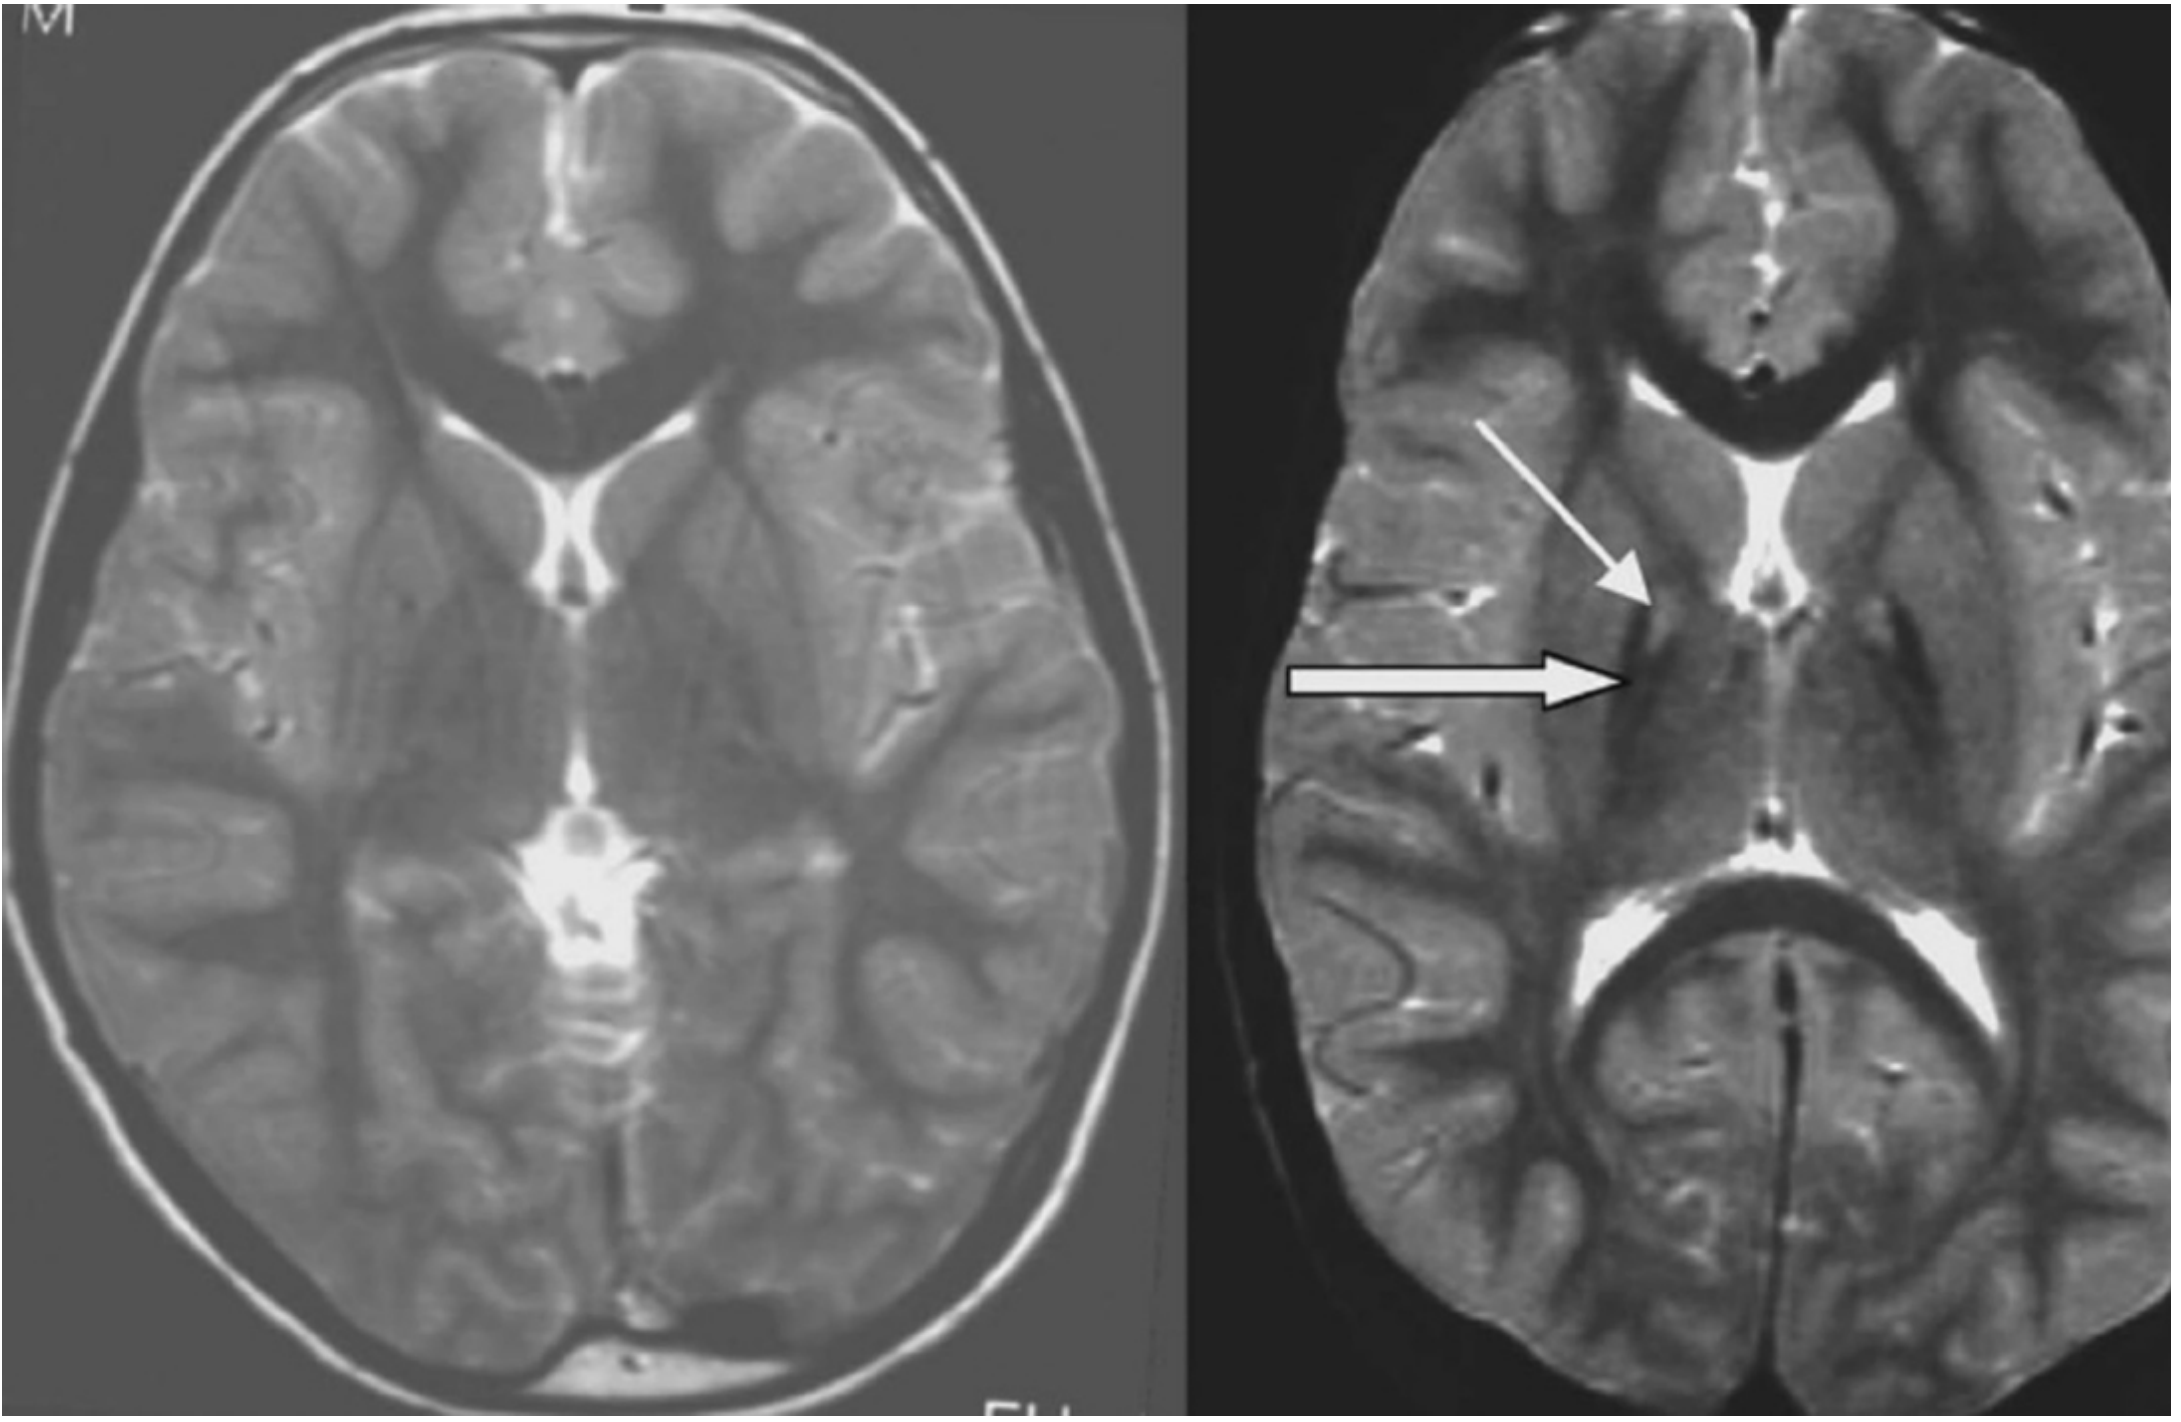

"Eye of the Tiger" Sign (PKAN hallmark on MRI)

Eye of the tiger sign — T2-weighted MRI showing bilateral hypointensity (iron) surrounding central hyperintensity in the globus pallidus in PKAN

Left: normal control. Right: PANK2 mutation-positive NBIA patient showing hypointensity (thick arrow = iron deposition) with central hyperintensity (thin arrow = axonal spheroids) in the medial globus pallidus — the "eye of the tiger" sign.